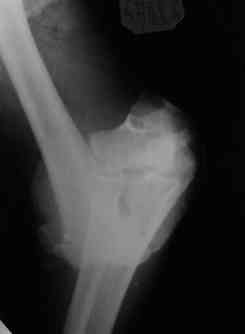

Уважаемые коллеги! Мужчина, 49 лет, упал 2 недели назад, будучи около полугода в запое. Сразу припоступлении рана промыта а-ля пульсирующая струя" до 8 литров и стабилизация (без ушивания раны). Через 2 дня пациент покинул отделение, думаю, что сражался с рогатыми животными, еще через 4 дня победив всех врагов пришел как путный с поникшей головой. На настоящий момент рана с обильным гнойным отделяемым в виде комков, но повязка стала промокать меньше, температура субфебрильная 4 дня и выше 37,3 не поднималась, боли умеренные, больше ночью. Есть несколько вопросов: 1.Нужна ли сейчас ревизия и дебридмент? 2.Оптимальный вариант дренирования? (сейчас просто резиновые выпускники, в т.ч. через онтраппертуру). 3.Нижний стержень находиться в очаге. Его необходимо убрать? Если да, то вариант фиксации.Жалко свою работу. Может общими усилиями спасем? ;) Спасибо. С уважением, Алексей.

Если нет нагноения его канала, то убирать его не надо. Однако фиксация не сильно надежная, может, хоть задней гипсовой шиной дополнить. Или наложить секцию на предплечье.

Уважаемые коллеги. Внешний вид конечности через 5 недель после травмы. Рана гранулирует, отделяемое скудное. Прошу строго не судить за внешний вид АВФ: ну нет пока у нас параллельных зажимов (приходиться выкручиваться).